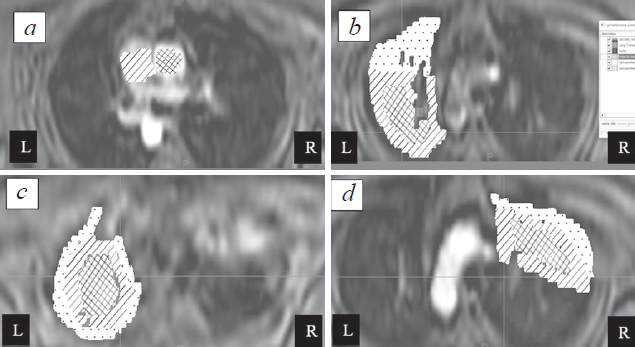

Materials and methods. 10 volunteers with no signs of interstitial lung disease were examined by three-dimensional ultrafast dynamic contrast-enhanced MR imaging using 3D T1-weighted images. The values of pulmonary blood flow (PBF), mean transit time (MTT), and pulmonary blood volume (PBV) for the targeted regions of interest were calculated based on the dynamic image series. For calculations, arterial input function (AIF) was used, as well as the time-intensity curves.

Results. The values of PBF, MTT, and PBV showed statistically significant differences between central and peripheral sections of lungs. Provided model can be implemented for quantitative assessment of regional pulmonary perfusion allows it to be used to determine the reliability of PBF, MTT and PBV values.